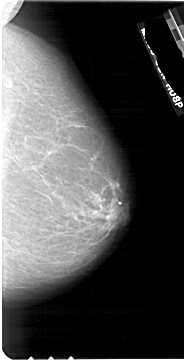

A_1884_1.LEFT_CC

LEFT_CC LINES 5356 PIXELS_PER_LINE 2986 BITS_PER_PIXEL 12 RESOLUTION 43.5 OVERLAY